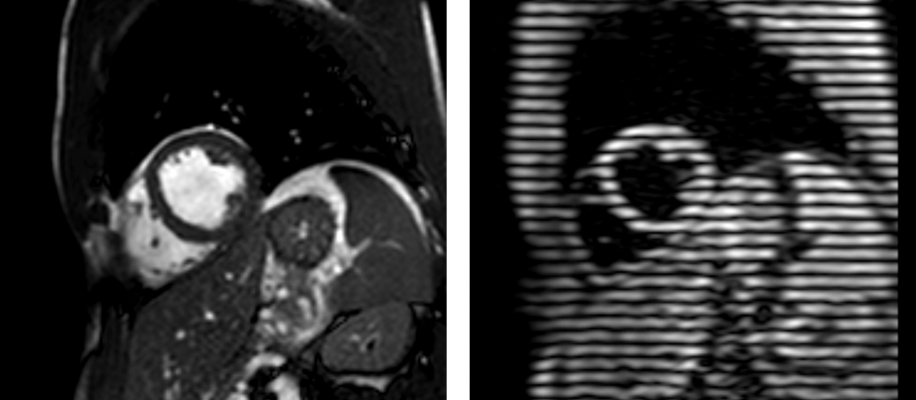

To visualize cardiac magnetic resonance tagging, cross-section of the heart in common imaging technique is seen on the left and tagged myocardium using CSPAMM on the right.

For the study, which is ongoing, Dörner and colleagues used cardiac magnetic resonance imaging (MRI) to measure the effect of energy drink consumption on heart function in 18 healthy volunteers, including 15 men and three women with a mean age of 27.5 years. Each of the volunteers underwent cardiac MRI before and one hour after consuming an energy drink containing taurine (400 mg/100 ml) and caffeine (32 mg/100 ml).

Compared to the baseline images, results of cardiac MRI performed one hour after the study participants consumed the energy drink revealed significantly increased peak strain and peak systolic strain rates in the left ventricle of the heart.